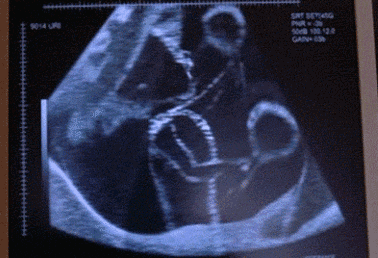

孕妇孕4-5个月感觉到胎动,孕5-6个月的时候,胎动比较明显,不仅胎动次数增加,力度也大了不少,很多孕妇明显感觉到胎儿在肚子里拳打脚踢,翻跟头;孕6-7个月的时候,胎儿越来越大,力气变大,而且宫内空间跟羊水量都非常充足,胎儿会在肚子里自由活动,一会儿游个泳,一会儿翻个滚,还会伸伸懒腰,晃晃小腿,爬行一会儿,拳打脚踢,各式各样的胎动,特别好玩。